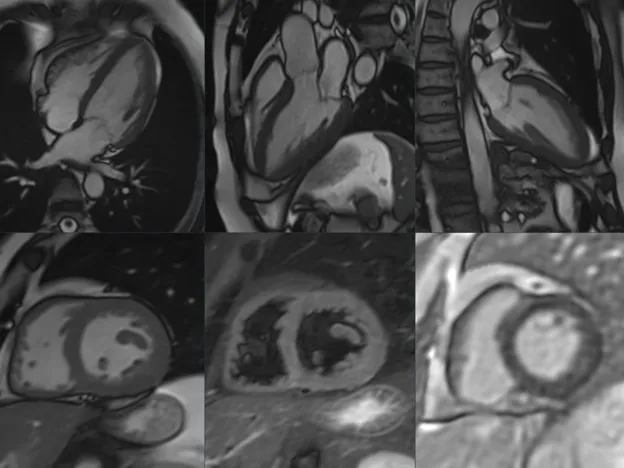

This training is accredited by EACCME with 9 CME credits This 3 half-day online course provides a comprehensive introduction to Cardiovascular Magnetic Resonance (CMR) for radiologists and cardiologists. The program combines expert-led lectures with individual case readings and interactive group discussions, allowing participants to gain both theoretical knowledge and practical experience.

Through real-life clinical cases, participants will learn to recognized typical imaging patterns in ischemic and non-ischemic cardiomyopathies (incl. Dilated cardiomyopathies, Hypertrophic cardiomyopathies, Infiltrative cardiomyopathies and others), myocarditis, pericardial disease, cardiac masses and valvular disease. The course emphasised structured interpretation, reporting, and clinical relevance of CMR findings.